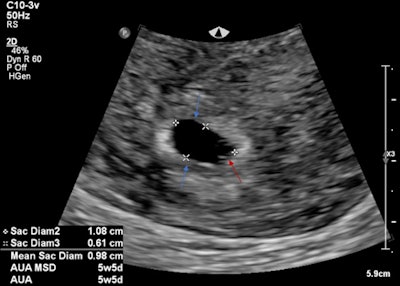

A 19-year-old female presented with suprapubic pain and a positive beta HCG. The initial ultrasound findings demonstrated both an intrauterine pregnancy and nonspecific adnexal mass. The intrauterine gestational sac featured both a gestational and yolk sac but no fetal pole. This correlated to an estimated gestational age of 5 weeks and 5 days. A heterogeneous left adnexal structure was demonstrated without internal vascularity. The left ovary was not readily identified. A hemoperitoneum was also present. The differential for the adnexal mass was thought to include a ruptured hemorrhagic cyst along with ovarian torsion and heterotopic pregnancy (see figures below).

Intrauterine gestational sac (blue arrows) and yolk sac (red arrow). No fetal pole identified.